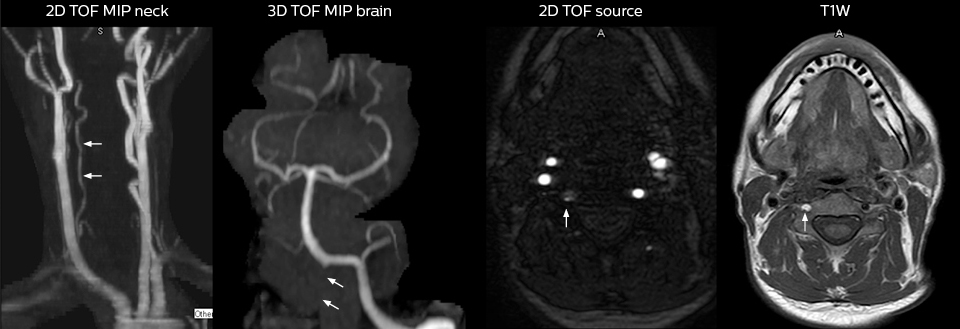

For Dr. Karis, the next goals for the neuro ED include converting the exams for acute stroke and TIA patients from CT to MRI, offering an alternative management option for these patients. Also, collaboration between other departments is currently underway, encouraging the performance of targeted exams with the ED MRI. These improvements in workflow and faster turnaround times may result in further reductions in scanning time.

2. Grimm JM, Schindler A, Schwarz F, Cyran CC, Bayer-Karpinska A, Freilinger T, Yuan C, Linn J, Trelles M, Reiser MF, Nikolaou K, Saam T. Computed tomography angiography vs 3 T black-blood cardiovascular magnetic resonance for identification of symptomatic carotid plaques. J Cardiovasc Magn Reson. 2014;16:84.